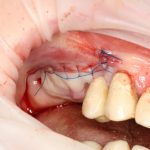

Кстати, обрати внимание на ширину альвеолярного гребня (левая картинка). Она чуть меньше 3 мм. Это объясняет, почему я засомневался в возможности установки имплантатов одновременно с остеопластикой. Понятно и без КЛКТ.

Возвращаемся к основной операционной области. Еще раз посмотрим на альвеолярный гребень, поофигеваем от его ширины и моих грандиозных планов:

Я зафиксировал костный блок практически без адаптации на несколько винтов. Обрати внимание, что винты находятся в зоне, где не планируется установка имплантатов. Фиксация должна быть надежной, поскольку мне еще предстояла подготовка лунок для имплантатов. Трех винтов для этого вполне достаточно.

Глянем на то, что получилось: